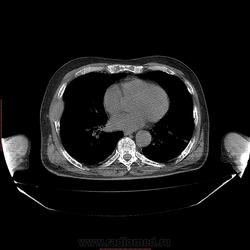

Пациент 1946 г.р., состоит на Д учете в онкодиспансере по поводу с-ч кожи (базалиома), прошел курс лучевой терапии, в 2009г на Ргенографии выявили образование 7 ребра, направили на Кт, на КТ (2009г) был выставлен д-з ГКО, пункционная биопсия не произведена. А сейчас вот такая картина, с множественными литическими очагами в костях грудного склета + образование 7 ребра, с отрицательной динамикой.

повторно взяли пациента, сняли кости таза, такая же картина- множественные очаги литической деструкции. Заключение: больше данных за миеломную болезнь.